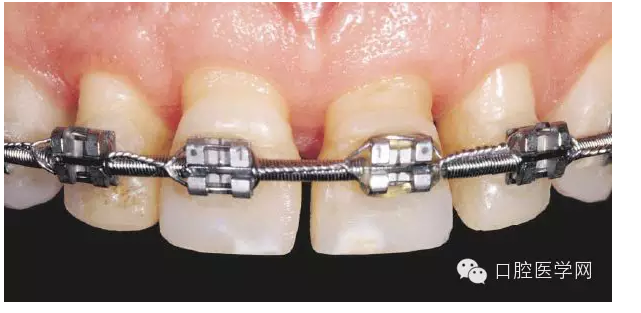

我個(gè)人對(duì)于牙周的理解是先是刺激>炎癥>吸收這樣一個(gè)過程(我個(gè)人理解,希望有懂牙周出來指正一下)。所以我覺得牙周醫(yī)生應(yīng)該是先祛除刺激,然后消除炎癥。當(dāng)然,一些患者在治療后會(huì)出現(xiàn)更嚴(yán)重的吸收,不過我認(rèn)為這是牙周炎癥的消失,對(duì)長久的來說是好事。下圖是第一張照片治療后的牙周情況,正畸是為了重新分布間隙做修復(fù)。